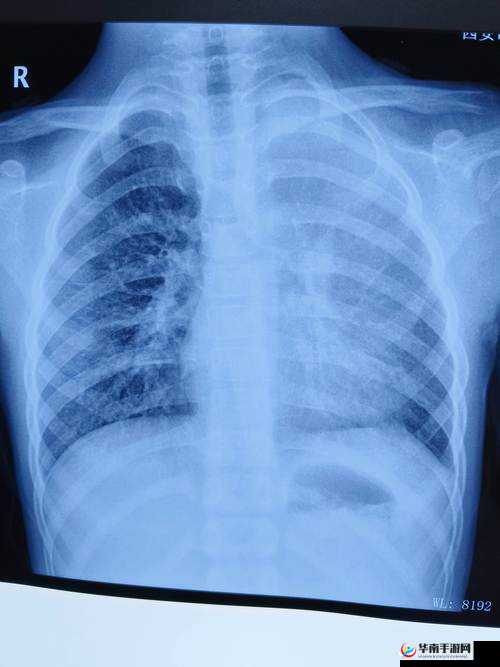

胸片,全称胸部 X 光片,是一种常用的医学影像检查方法。它通过 X 线束对胸部进行照射,然后将穿过胸部的 X 线束投影在胶片或探测器上,形成黑白对比的影像。胸片可以帮助医生观察胸部的结构、形态、大小以及肺部的情况,包括肺部纹理、心脏大小、纵隔情况等。

胸片全体曝光的优点之一是能够早期发现肺部疾病。许多肺部疾病在早期阶段可能没有明显的症状,但通过胸片检查,医生可以发现一些细微的变化,如肺部结节、肺炎、肺气肿等。这些早期发现对于及时治疗和提高治愈率非常重要。

胸片还可以用于检测胸部的其他异常情况,如肋骨骨折、胸腔积液、纵隔肿瘤等。对于长期吸烟、有肺癌家族史或其他高危因素的人群,定期进行胸片检查可以帮助早期发现肺癌,提高治愈率和生存率。